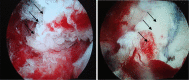

Methods: Both the avulsed bone block and the tibia bone bed were refreshed. The procedure was completed with the assistance of PCL director drill guide. The reduction and fixation using high-strength line were used to fix the avulsed bone by from posterior middle portal. Rehabilitation began early postoperatively.

Results: From January 2010 to June 2012, a total of 18 arthroscopically treated cases of PCL tibial avulsion fracture were retrospectively evaluated. Reduction of the avulsion fragment was obtained in all cases. 16 cases were followed up for 7-30 months (average 13.6), and 2 cases were out of follow-up. In the 16 followed patients, flexion and extension were back to normal within 6 weeks, and return to normal walk in 12 weeks. The bone healing was good without any vascular or nerve complications. All the patients regained the preinjury activity level. The mean score (and standard deviation) increased from 38.9 ± 4.9 points to 95.2 ± 3.8 points with the system of Lysholm, from 57.1 ± 10.3 points to 94.3 ± 4.4 points with the system of IKDC. Post-test displacement of KT3000 declined from 3.6 ± 0.39 to 1.1 ± 0.27 mm.